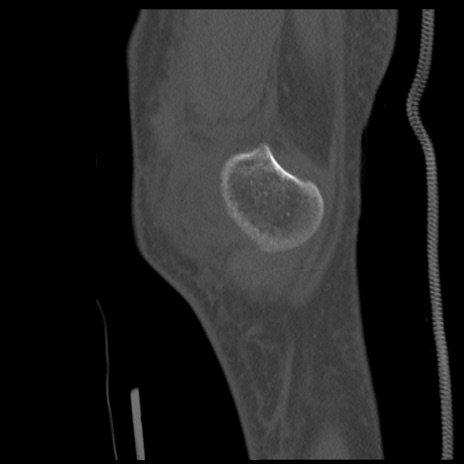

症例28 右膝関節CT(矢状断像)

右膝関節CT